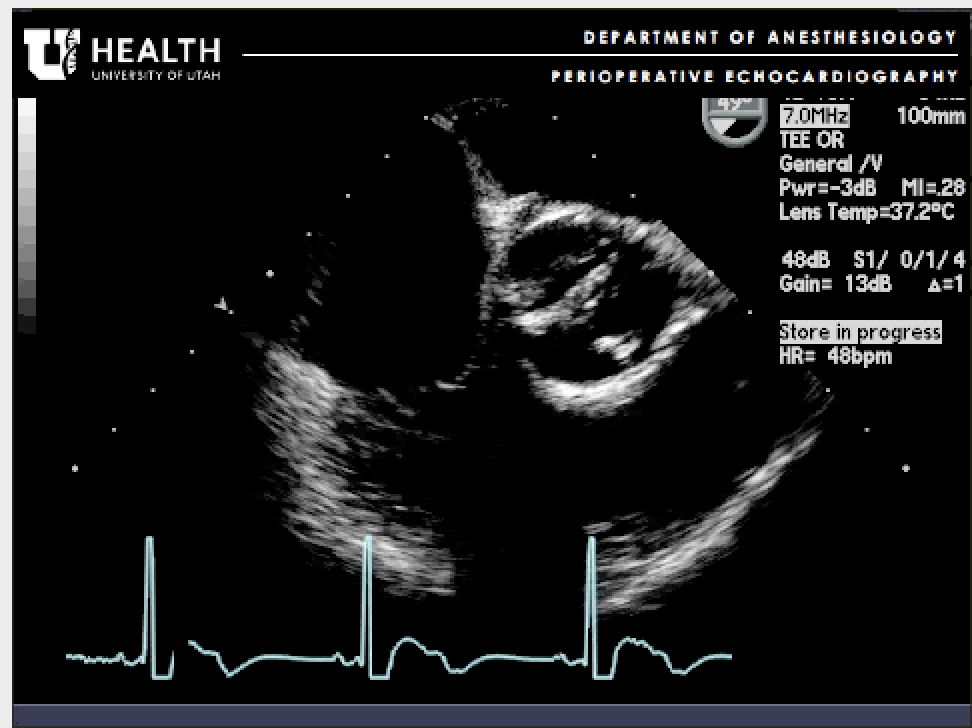

What is this? What else should be checked for?

Bicuspid Aortic Valve. RCC and LCC fused.

Should look for coarctation of aorta and dilation of ascending aorta